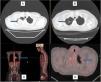

We report the case of a 49-year-old woman, former smoker with a pack-year index of 2, and a history of hypothyroidism. Her regular treatment was levothyroxine 75 mcg, 1 tablet a day. She attended the emergency department due to headache following an episode of sinusitis, with no associated respiratory symptoms. The baseline study included a standard chest X-ray, which revealed an incidental finding of a right apical lesion of irregular contours. An initial CT scan was requested that revealed a “rounded tumor mass in the right lung vertex, irregular contours, lobulated and spiculated towards the surrounding parenchyma. Lesion with heterogeneous enhancement with contrast, in extended contact with the posterior and superior apical pleura, measuring about 45×42mm, with no evidence of pleural or extrapleural infiltration or extension; at the apex of the left lung, a small, nodular subpleural, lesion measuring less than 1cm of dubious significance is observed”. In light of these findings, positron emission tomography was performed. This highlighted the presence of this lesion, which was metabolically active with a maximum standardized uptake value (standarized SUVmax) of 27.5, and the lesion in the left upper lobe, which had an SUVmax of 7.5. Bilateral hilar adenopathies were seen in the mediastinum, in particular a left hilar conglomerate measuring 3.2×2.1×4.1cm with a SUVmax of 14.1 (Fig. 1). Given the high suspicion of malignancy, we decided to conduct a core needle biopsy of the larger lesion, the result of which showed the presence of fibrosis and polymorphous lymphohistiocytic exudate suggestive of an inflammatory process or inflammatory pseudotumor. The molecular study was negative for EGFR gene mutations, but genetic studies were not performed for ALK. Tumor markers (CEA, CA 15.3, CA 19.9, CYFRA-21, squamous cell carcinoma Ag, Pro-GAP, and enolase) were negative. No anemia or thrombocytosis was detected. These results needed to be confirmed by a repeat core needle biopsy, which provided a similar diagnosis. We also performed fiberoptic bronchoscopy, which revealed mucosal thickening of inflammatory appearance in the left lower lobe. Blind bronchial brushing was performed of this region, yielding no neoplastic cells. In the absence of any suggestion of malignancy, and the existence of several lesions that prevented a surgical approach, we decided to start treatment with deflazacor at doses of 1mg/kg body weight per day for 2 months, tapering to half in the following 2 months, and discontinuing the following month. Three computed axial tomography scans were performed during treatment, showing a progressive decrease in tumor size, as well as the presence of linear tracts of fibrotic scar tissue and traction bronchiectasis in the area, with disappearance of the contralateral nodule.

Computed axial tomography image at diagnosis (A) and after treatment with corticosteroids (B), showing remission of the lesion in the right upper lobe, with some remnants of residual fibrous tracts (arrows). PET-CT image with enhanced uptake in the left pulmonary hilum (C) and in the left upper lobe (D), marked by arrows, reflecting the multilocular involvement of this case.